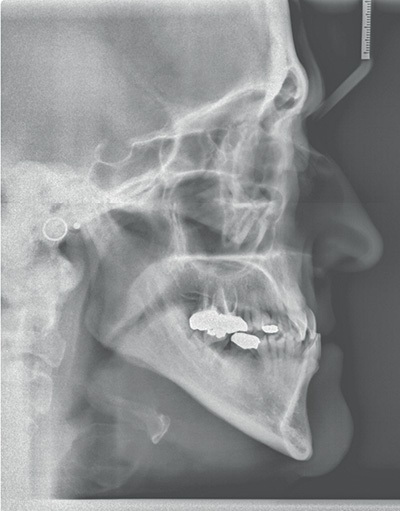

Diagnosing from “outside-in,” she showed lower 1/3 vertical facial height in slight excess, a prominent chin and mild mandibular asymmetry to the right. Unfavorable dark triangles are obvious in her smile because of periodontal recession. She shows only mild Class III occlusion, but a significant number of teeth are in full crossbite position. Notable cephalometric findings include mild mandibular prognathism, a high mandibular plane angle and lower incisors that are slightly compensated/upright as you might expect with a Class III excess mandible. Multiple areas of varying bone loss are present and the LR8 was given a poor long-term prognosis by the dentist.

I felt that choosing to place the bite turbos on posterior teeth would be unfavorable for two reasons. First, posterior turbos tend to limit posterior extrusion and overall vertical opening. Posterior extrusion and vertical opening of the MPA alone favor occlusal correction of Class III to Class I and underbite correction as the lower jaw rolls slightly down and back. Second, in Shelley’s case, if the posterior teeth were intruded at all, great care would be needed at the end of treatment to make sure that these teeth completely settled into full contact to prevent a harder than ideal occlusion on the anterior teeth (the lower incisors show significant periodontal loss).

Instead, the turbos were placed on the lower canines and first bicuspids. These teeth, and the maxillary canines that would abut them, showed relatively good periodontal support and longer roots. They could likely shoulder the concentrated masticatory load in this periodontally compromised patient for more than a few months of treatment if needed. Also the turbos were shaped into a ramp (they sloped in to the lingual) to give function to their form. As the maxillary canines (which were in crossbite) hit the ramps, there would be a labial crown-tipping effect to jump their position out of crossbite as the maxillary teeth aligned. Crossbite elastics also played an important role in this regard as well.